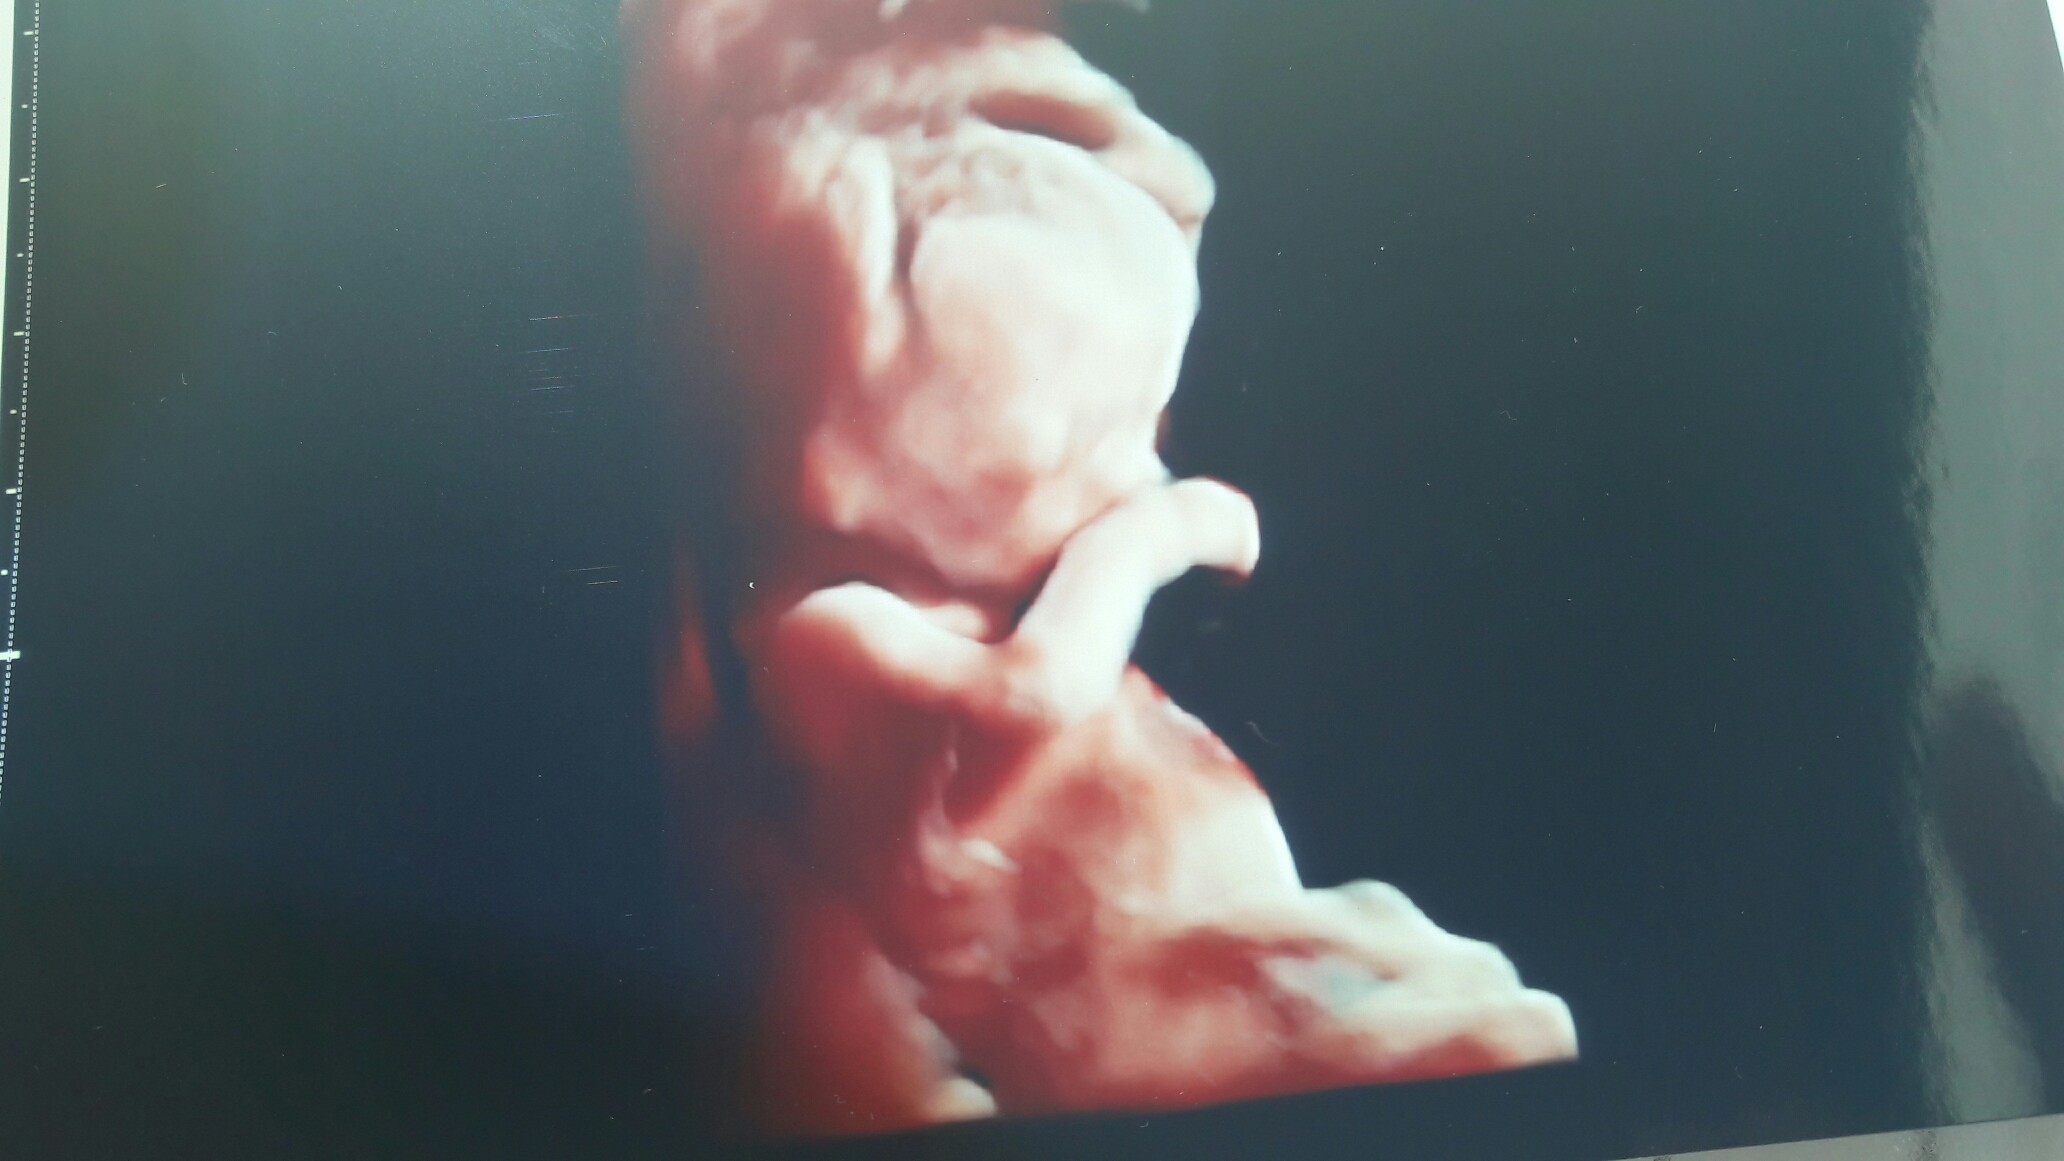

Cześć dziewczyny. Wiem, że byłam wpisana do kalendarza, więc przychodzę podzielić się kilkoma nowinkami. Testy genetyczne wyszły super. Badanie trwało ponad godzinę, bo lekarz wszystko szczegółowo opowiadał. Dzidzia ma 7 cm i prawie na pewno będzie dziewczynka. Wkraczamy więc powoli w 13 tydzień. Pozdrawiam. Czytam Was bardzo często, ale z ukrycia. Trzymam za Was wszystkie wielkie kciuki..

Cześć dziewczyny. Wiem, że byłam wpisana do kalendarza, więc przychodzę podzielić się kilkoma nowinkami. Testy genetyczne wyszły super. Badanie trwało ponad godzinę, bo lekarz wszystko szczegółowo opowiadał. Dzidzia ma 7 cm i prawie na pewno będzie dziewczynka. Wkraczamy więc powoli w 13 tydzień. Pozdrawiam. Czytam Was bardzo często, ale z ukrycia. Trzymam za Was wszystkie wielkie kciuki.. Zobacz załącznik 807784